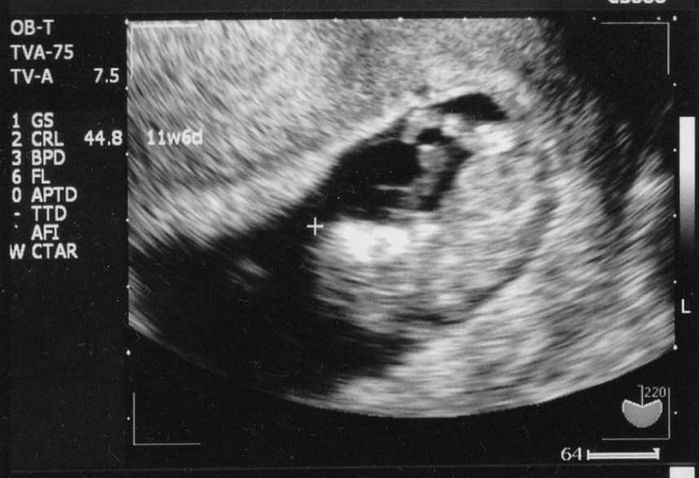

妊娠10週目のエコー写真

足が出来ました

へその緒が見えます。まだお腹に余裕があり動き回るころ。